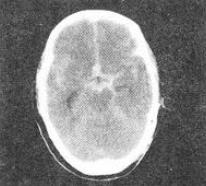

- 单项选择题3、 成人,外伤后1小时,CT检查如图,最可能的诊断是()。

A、正常脑CT

B、硬膜下血肿

C、蛛网膜下腔出血

D、硬膜外血肿

E、脑出血